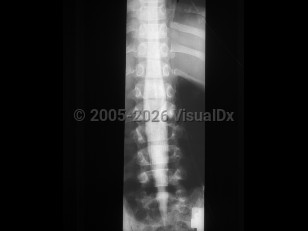

Osteoporotic vertebral compression fracture

Spondylolysis

Ankylosing spondylitis

Spondylolisthesis

Lumbar spinal stenosis

Adult spinal deformity

Osteoporosis